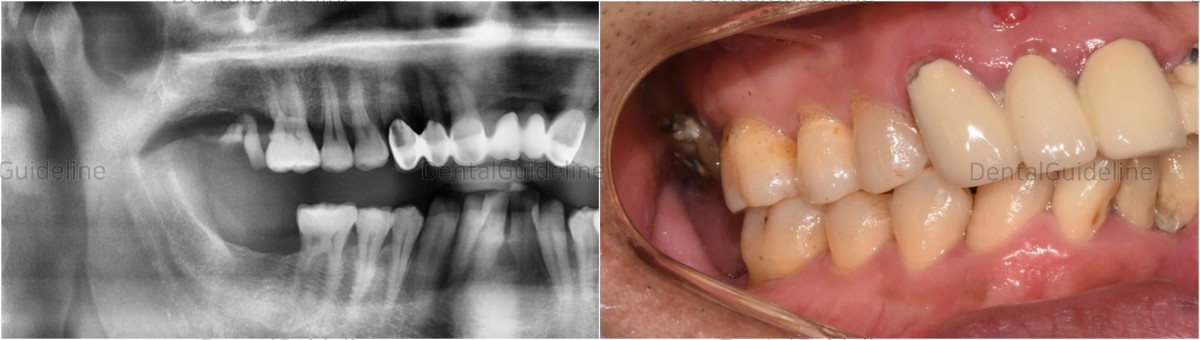

As a patient who needs implants in several parts, it was decided to complete the right side first to correct the occlusion in one part and to solidify the vertical stop.

-Pre-op intra-oral view.

- pre-op intraoral photo. 4 months after implant placement of opposing tooth.